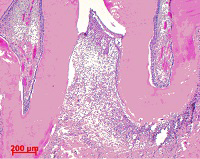

歯科治療の一例

提携 歯科技工所への発注 口腔外科疾患に対する処置

歯科口腔外科用器具による処置 歯肉処置の例

口腔外科に準じた処置 インプラントの埋入手術(上顎)